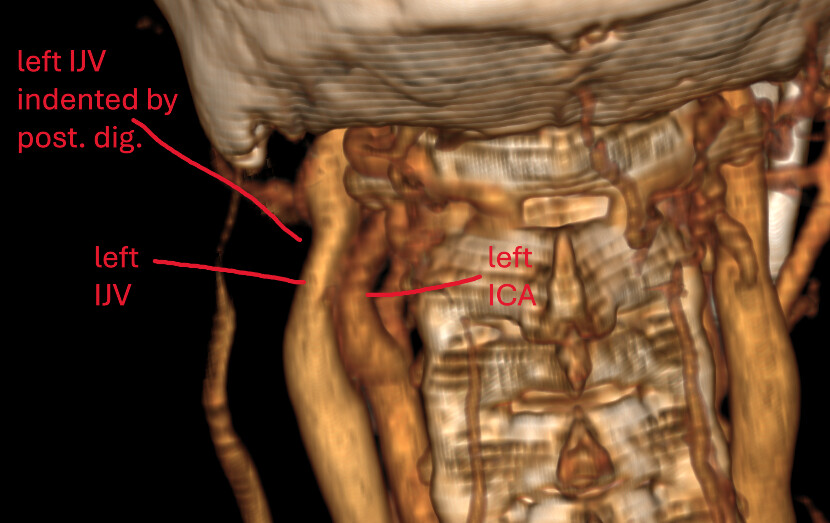

@chrEagle those are logical explanations I think! The compression by your digastric looks worse on the left (seen in image #3). Where I have labelled your left ICA and left IJV, the IJV is pancaked between the left ICA and the posterior digastric. The posterior digastric touches the right IJV as well, but compression is not as bad. I think it moreso has to do with your left ICA pushing your left IJV into the digastric. Because on the right side you don’t see compression by digastric, but you also don’t see compression by the ICA. So I think the tortuous left ICA is a pretty significant culprit here.

Interpretation: Classic extrinsic compression of the IJV between the left ICA and posterior digastric, forming a C1/digastric/ICA corridor. The IJV is trapped in this soft-tissue triangle, not a bony entrapment (i.e., not primarily due to styloid or C1).

You can actually see the tortuous left ICA run into the left IJV in the 3D model I posted:

@chrEagle I re-downloaded your CT to get better 3D images of the compression in question.

See attached. Hope this helps!